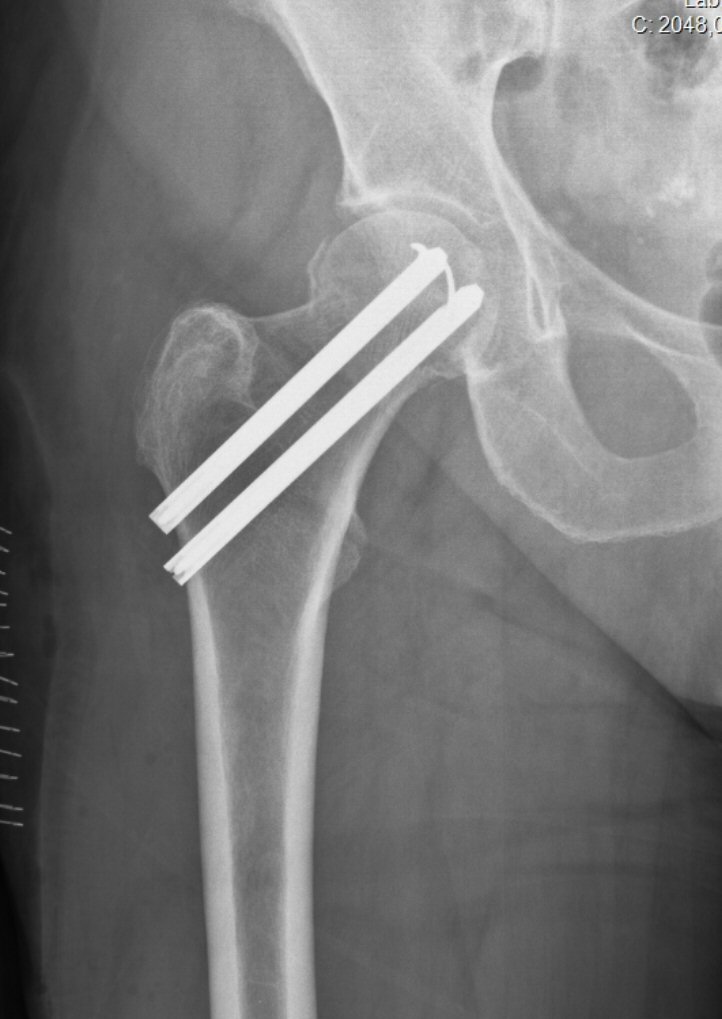

Kontrollröntgen med LIH-spikar i bra lägen: parallella, lagom långt inslagna, lagom långa, nära distala resp. dorsala kortex och med låsfjädrar i korrekta riktningar